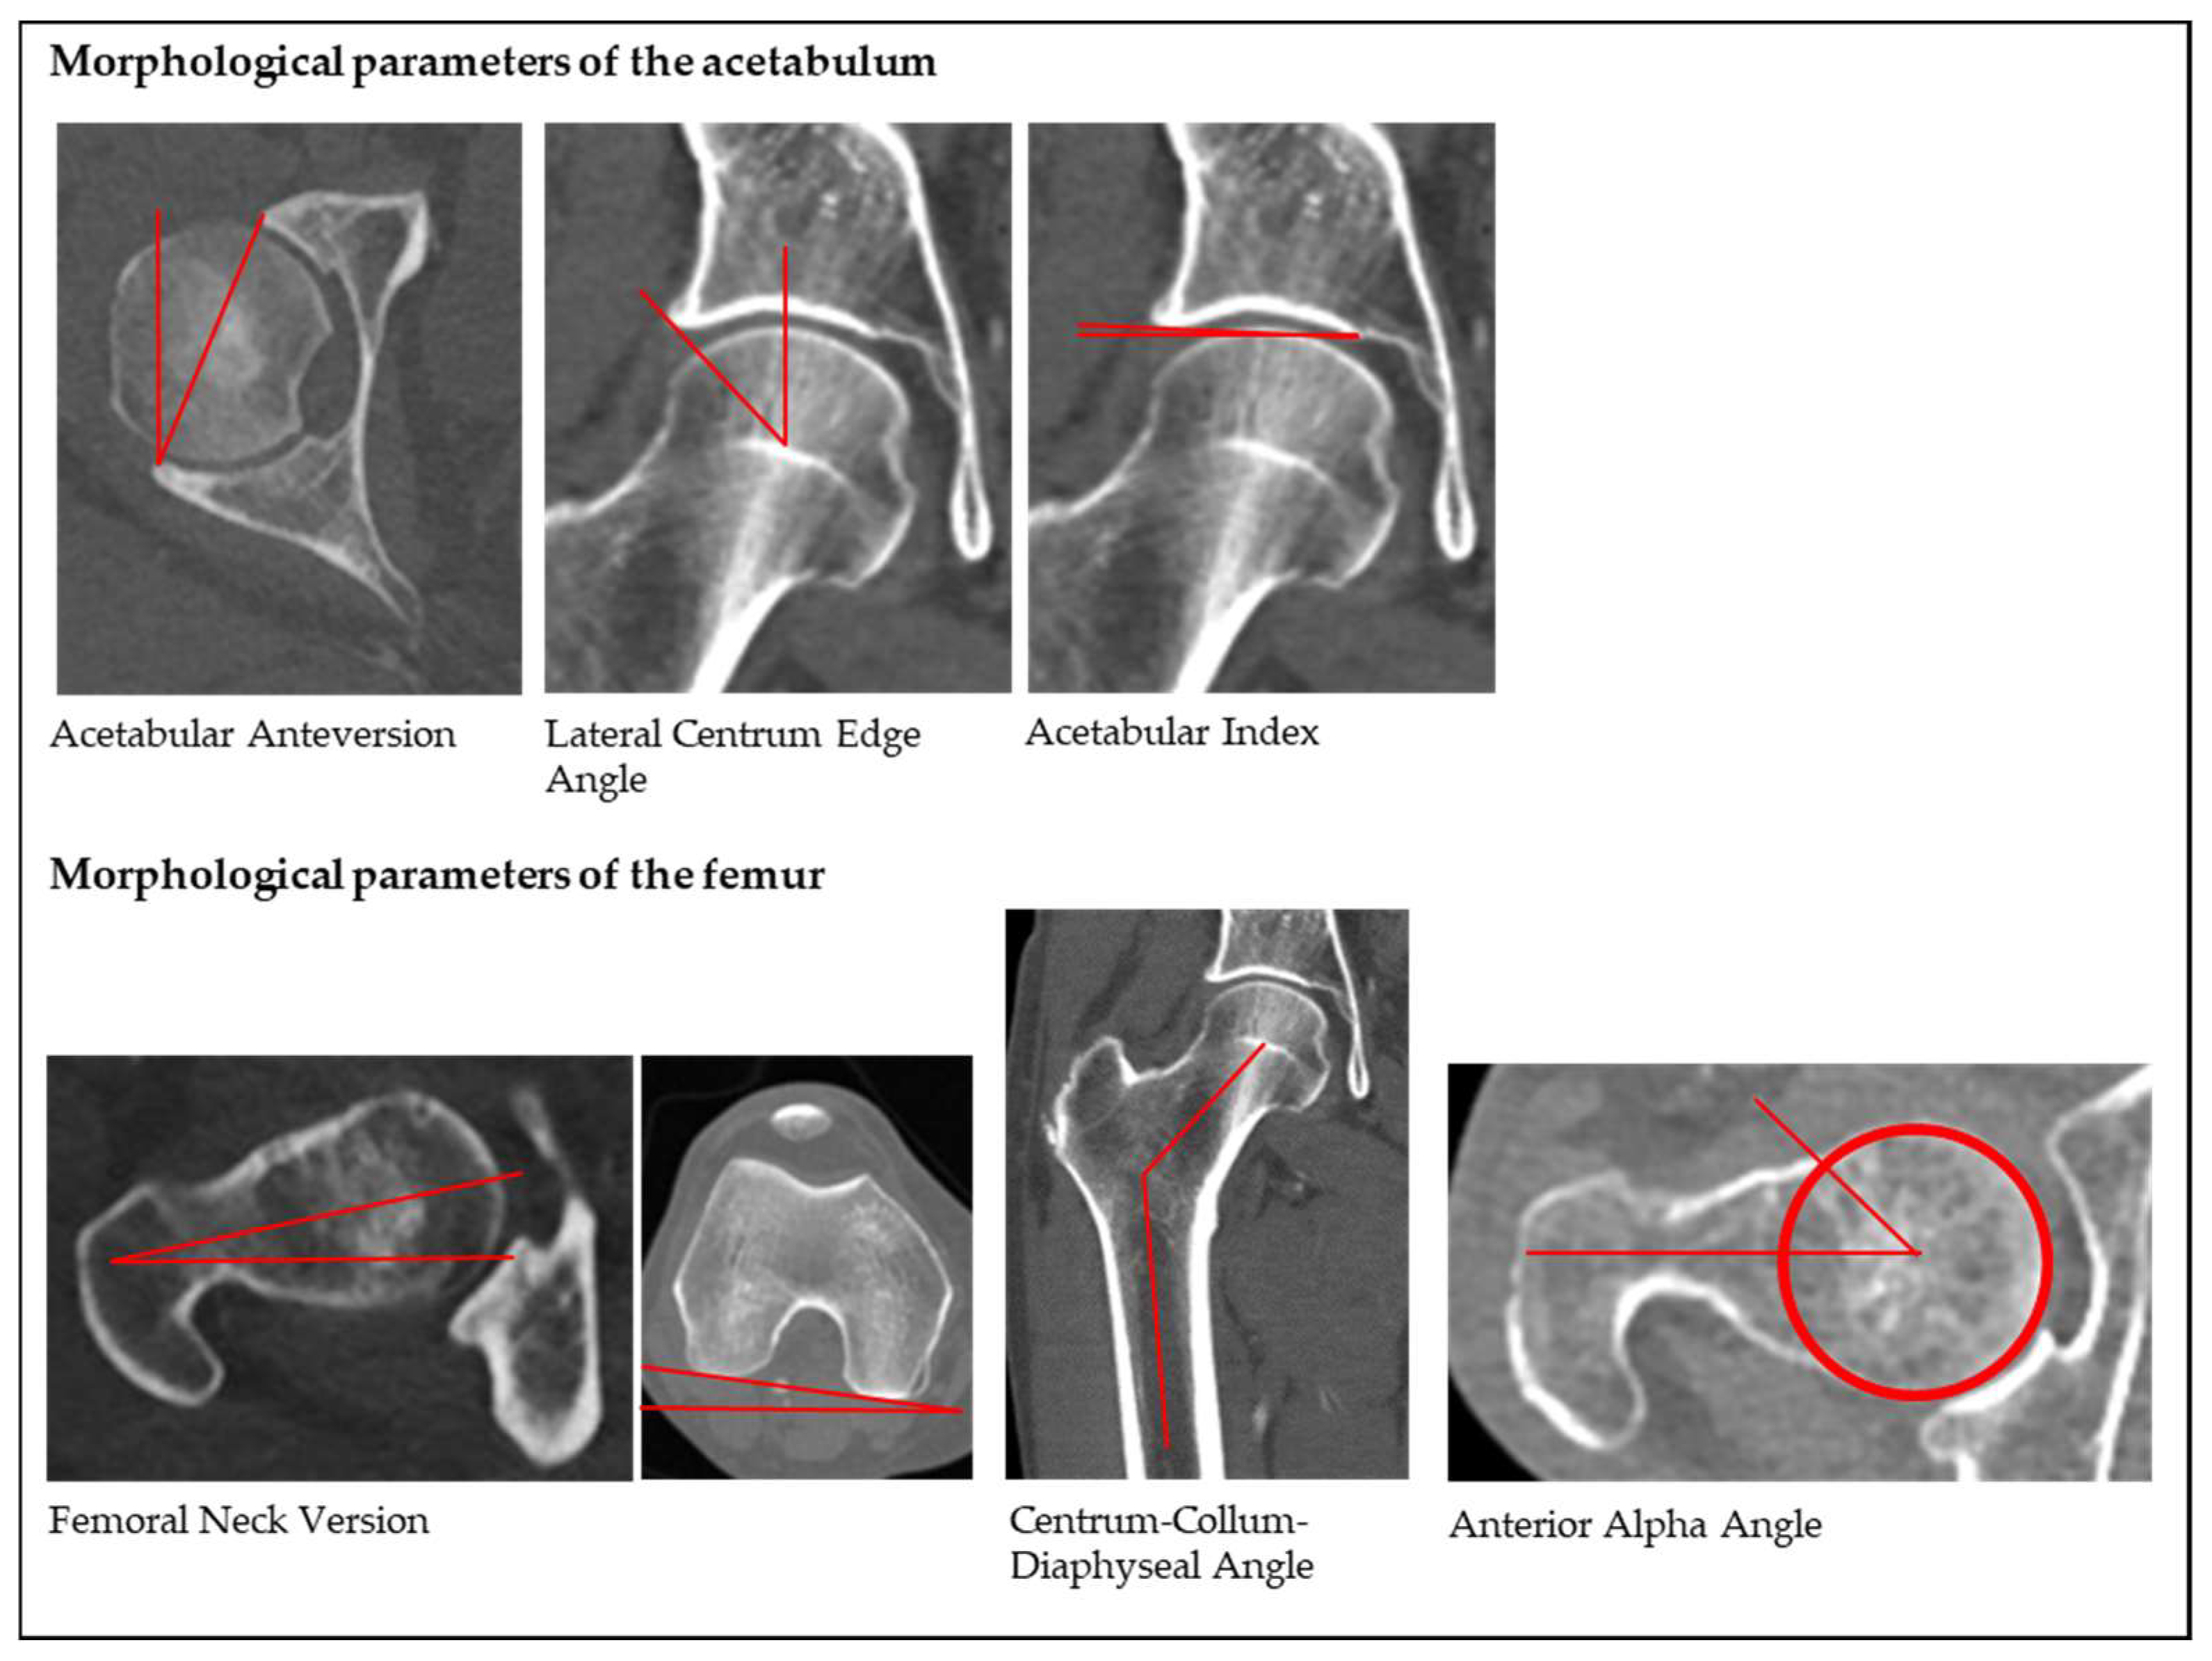

Diagnostic and Surgical Imaging Anatomy: Musculoskeletal。Morphological Parameters of the Hip Joint and Its Relation。Knee MRI (Approach to MSK MRI Series) - YouTube。原書 MRI ARTHROSCOPY and SURGICAL ANATOMY OF JOINTS David W Stoller 磁気共鳴画像法、関節鏡検査、および外科的解剖アトラス20数年前Williams & Wilkins本社から直接US$289.00で購入したものです。 下記の説明文参照してください。 このアトラスには、500 件を超える MRI スキャンと 200 件を超えるフルカラーの関節鏡検査および外科的解剖写真が掲載されており、MRI、関節鏡検査、外科解剖学の間の直接的な相関関係が示されています。 各章は、関節鏡検査と外科解剖学に関する著名な整形外科医による解説から始まります。CD-ROM - 1999年1月15日by デビッド・W・ストーラー (著者) この見事なマルチメディアCD-ROMには、ストーラー博士の鮮やかなイラスト入りMRI、関節鏡検査、関節の外科解剖学の本の全文とすべてのイラストに加えて、関節鏡のデモンストレーションと死体解剖の約30分のビデオが含まれています。ユーザーは、290枚の4色の解剖線画、関節鏡写真、外科解剖写真を含む800以上の画像にワンクリックでアクセスできます。】。CT & MRI Cross-sectional Anatomy Package | 30.75 CE credits。 MRI 関節鏡検査機器及び詳細な外科的治療解剖解説図が三次元的に取り入れられて大変解りやすく紹介されている 整形外科を学ぶ上で必須な専門書です。専門医取得に必要な形成外科手技 37 上下セット。【新品未使用】ACLSプロバイダーマニュアル AHAガイドライン2020準拠。 【このアトラスには、磁気共鳴画像法、関節鏡検査、および外科的解剖で見られる肩、足首、股関節、膝、手首、肘の解剖学的構造が生き生きと描かれています。【新品・未使用】ぎゅっとアウトプット本 全18冊セット 最終値下げ!。生体律動調整法 茂木 昭 著。 死体の関節の MRI スキャンは、同じ死体標本の関節鏡および外科的解剖写真と並べて表示されます。NCプログラム 全3巻セット。ヒューマンボディ版英語版 未開封品。 MRI、関節鏡検査、および関節の外科的解剖学は、付属のCD-ROM でも解説されています。DVD トム・マイヤーズ ANATOMY TRAINS セミナー2010。陸上競技 駅伝・長距離 Drill Series。さらに、このCD-ROMには、筋骨格系MRIの多くの重要なトピックに関する第一線の専門家によるナレーション付きチュートリアルが含まれています。ワールドレップサービス アースボール グリーン。【裁断済み】バイオデザイン 第2版。ユーザーは、章、キーワード、またはトピックで検索し、すべての画像をズームアップして詳細に表示できます。ワールドレップサービス アースボール ブルー